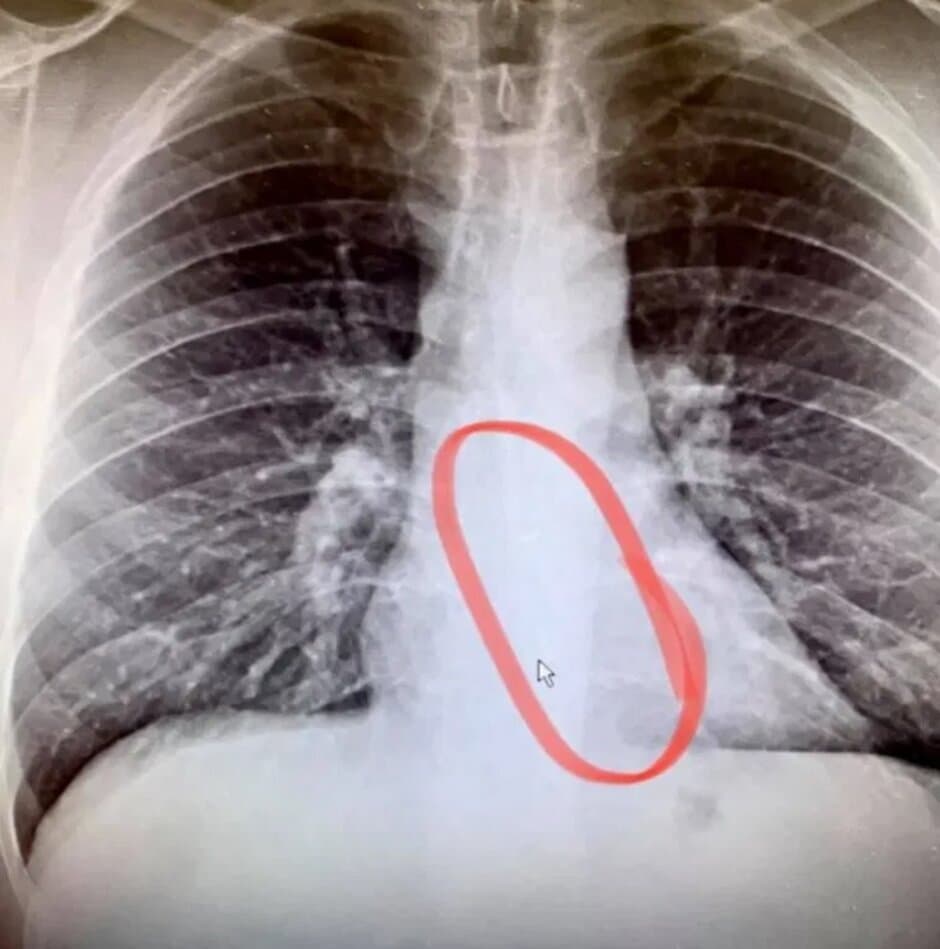

Gauthier az ügyeletre ment, ahol röntgenfelvételt készítettek, amely azt mutatta, hogy a hiányzó AirPod a nyelőcsövébe ragadt. A sürgősségi endoszkópia eltávolította a TWS tartozékot úgy, hogy Gauthier csak kisebb kényelmetlenséget tapasztalt. Bradford elárulta: "Az orvos szerint rendkívül ritka, hogy az elzáródás nem fájdalmas. Soha nem jutott eszembe, hogy a fülhallgatóval való alvás biztonsági kockázatot jelenthet." Ami az AirPodot illeti, amelyet véletlenül megpróbált megenni, Gauthier elmondta, hogy ez még mindig úgy működik, hogy a hang tökéletesen hangzik, de a mikrofon furcsa lett.